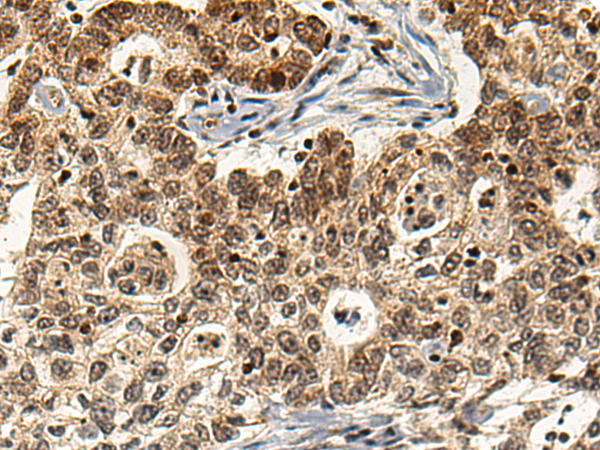

分类: 科研抗体货号: P01737别名: RISC; HSCP1应用: WB,IHC反应种属: Human, Mouse, Rat

分类: 科研抗体货号: P01680别名: LYP; PEP; LYP1; LYP2; PTPN8应用: IHC反应种属: Human, Mouse